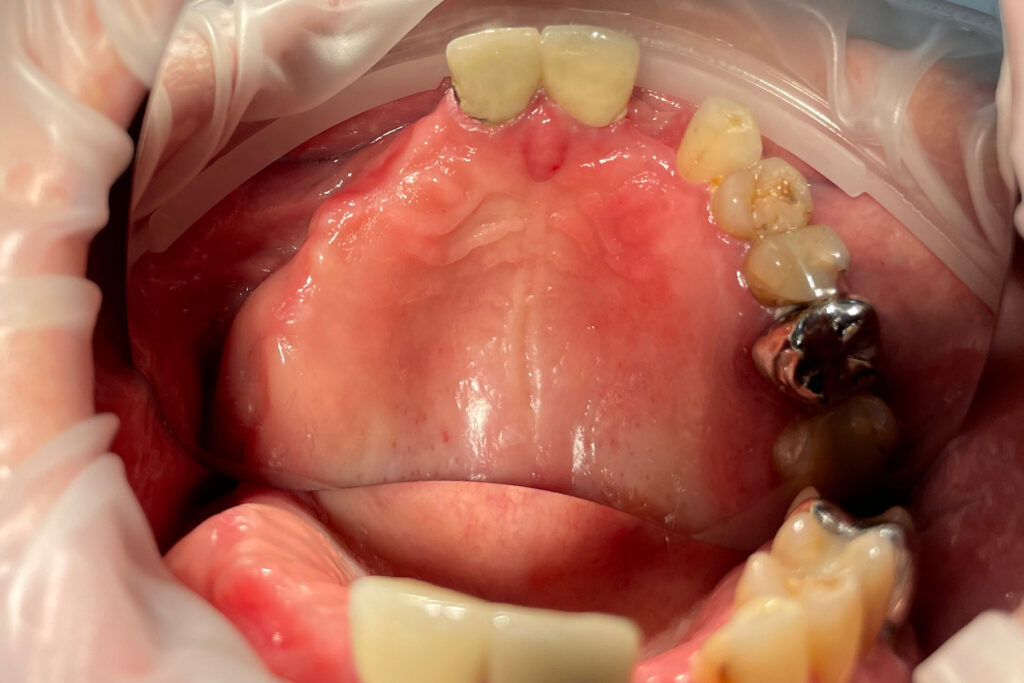

Ситуация до лечения

Жалобы: Пациент обратился к нам с целью проведения комплексной имплантации верхней челюсти.

Диагноз: Частичная вторичная адентия верхней челюсти.

пациент до протезирования

После консультации было принято решение об удалении зубов на верхней челюсти, которые находились в неудовлетворительном состоянии

и проведении комплексной имплантации по системе All-on-4.